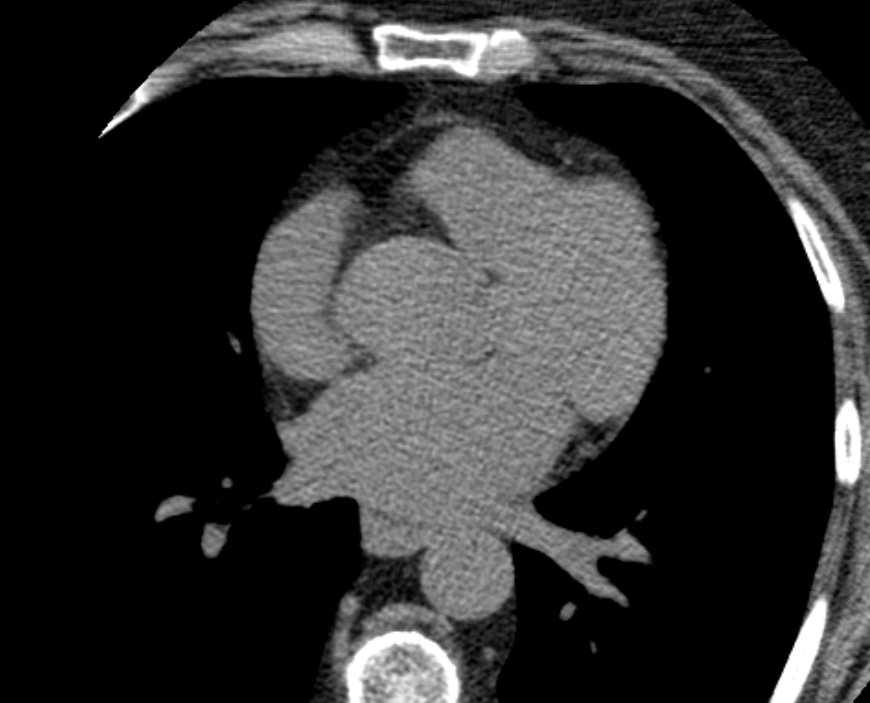

В нашей клинике исследование выполняется на новейшем 128-срезовом мультиспиральном компьютерном томографе экспертного класса TOSHIBA AQUILION CXL. Объектом данного исследования является сердце и коронарные артерии. Томограф производит послойное сканирование области сердца с шагом от 0,5 мм, и, благодаря высокой плотности отложения кальция и кальцинированные бляшки хорошо видны на снимках. За счет увеличенного количества сверхчувствительных детекторов сканирование происходит за несколько секунд, при этом доза рентгеновского облучения для пациента минимальна.

Для большей наглядности и определения точной локализации кальцинатов полученные при сканировании данные преобразуются аппаратом в объемные изображения сердца и сосудов.

Затем на основании полученных данных вычисляется индекс коронарного кальция (индекс Агатстона) для каждого коронарного сосуда в отдельности. Отсутствие кальция говорит о низком риске сердечно-сосудистых заболеваний.

Высокие показатели индекса кальция свидетельствуют о явном атеросклеротическом поражении коронарных артерий и образовании кальцинированных бляшек.